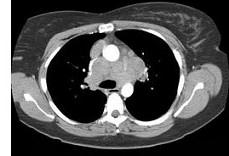

问题 女,33岁,咳嗽,乏力,低热,皮肤有结节,结合CT图像,最可能的诊断是 ( )

选项 A.肺结核 B.霍奇金病 C.非霍奇金病 D.结节病 E.肺癌

答案 D